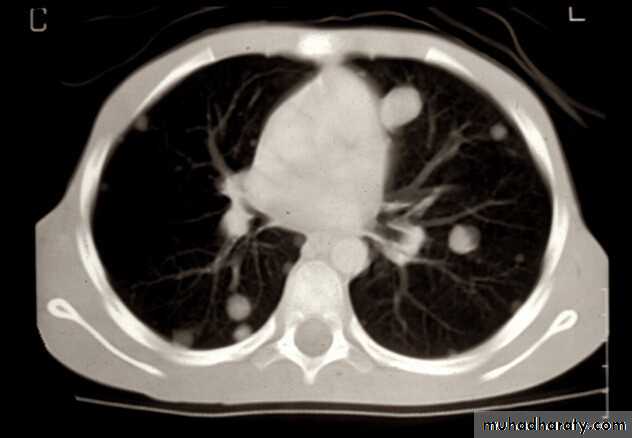

Presentation of Bone Tumors

Further radiographic evaluation may help with differential diagnosis of bone painBone scan

MRI

Chest CT scan

Metastases 20%